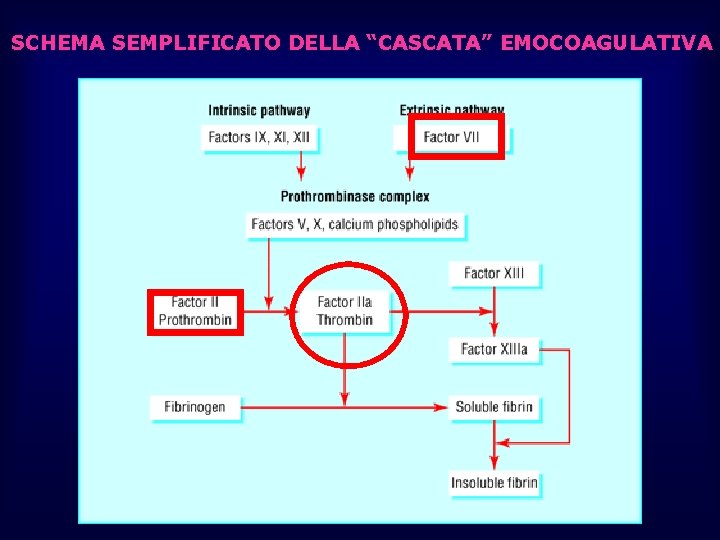

SCHEMA SEMPLIFICATO DELLA “CASCATA” EMOCOAGULATIVA